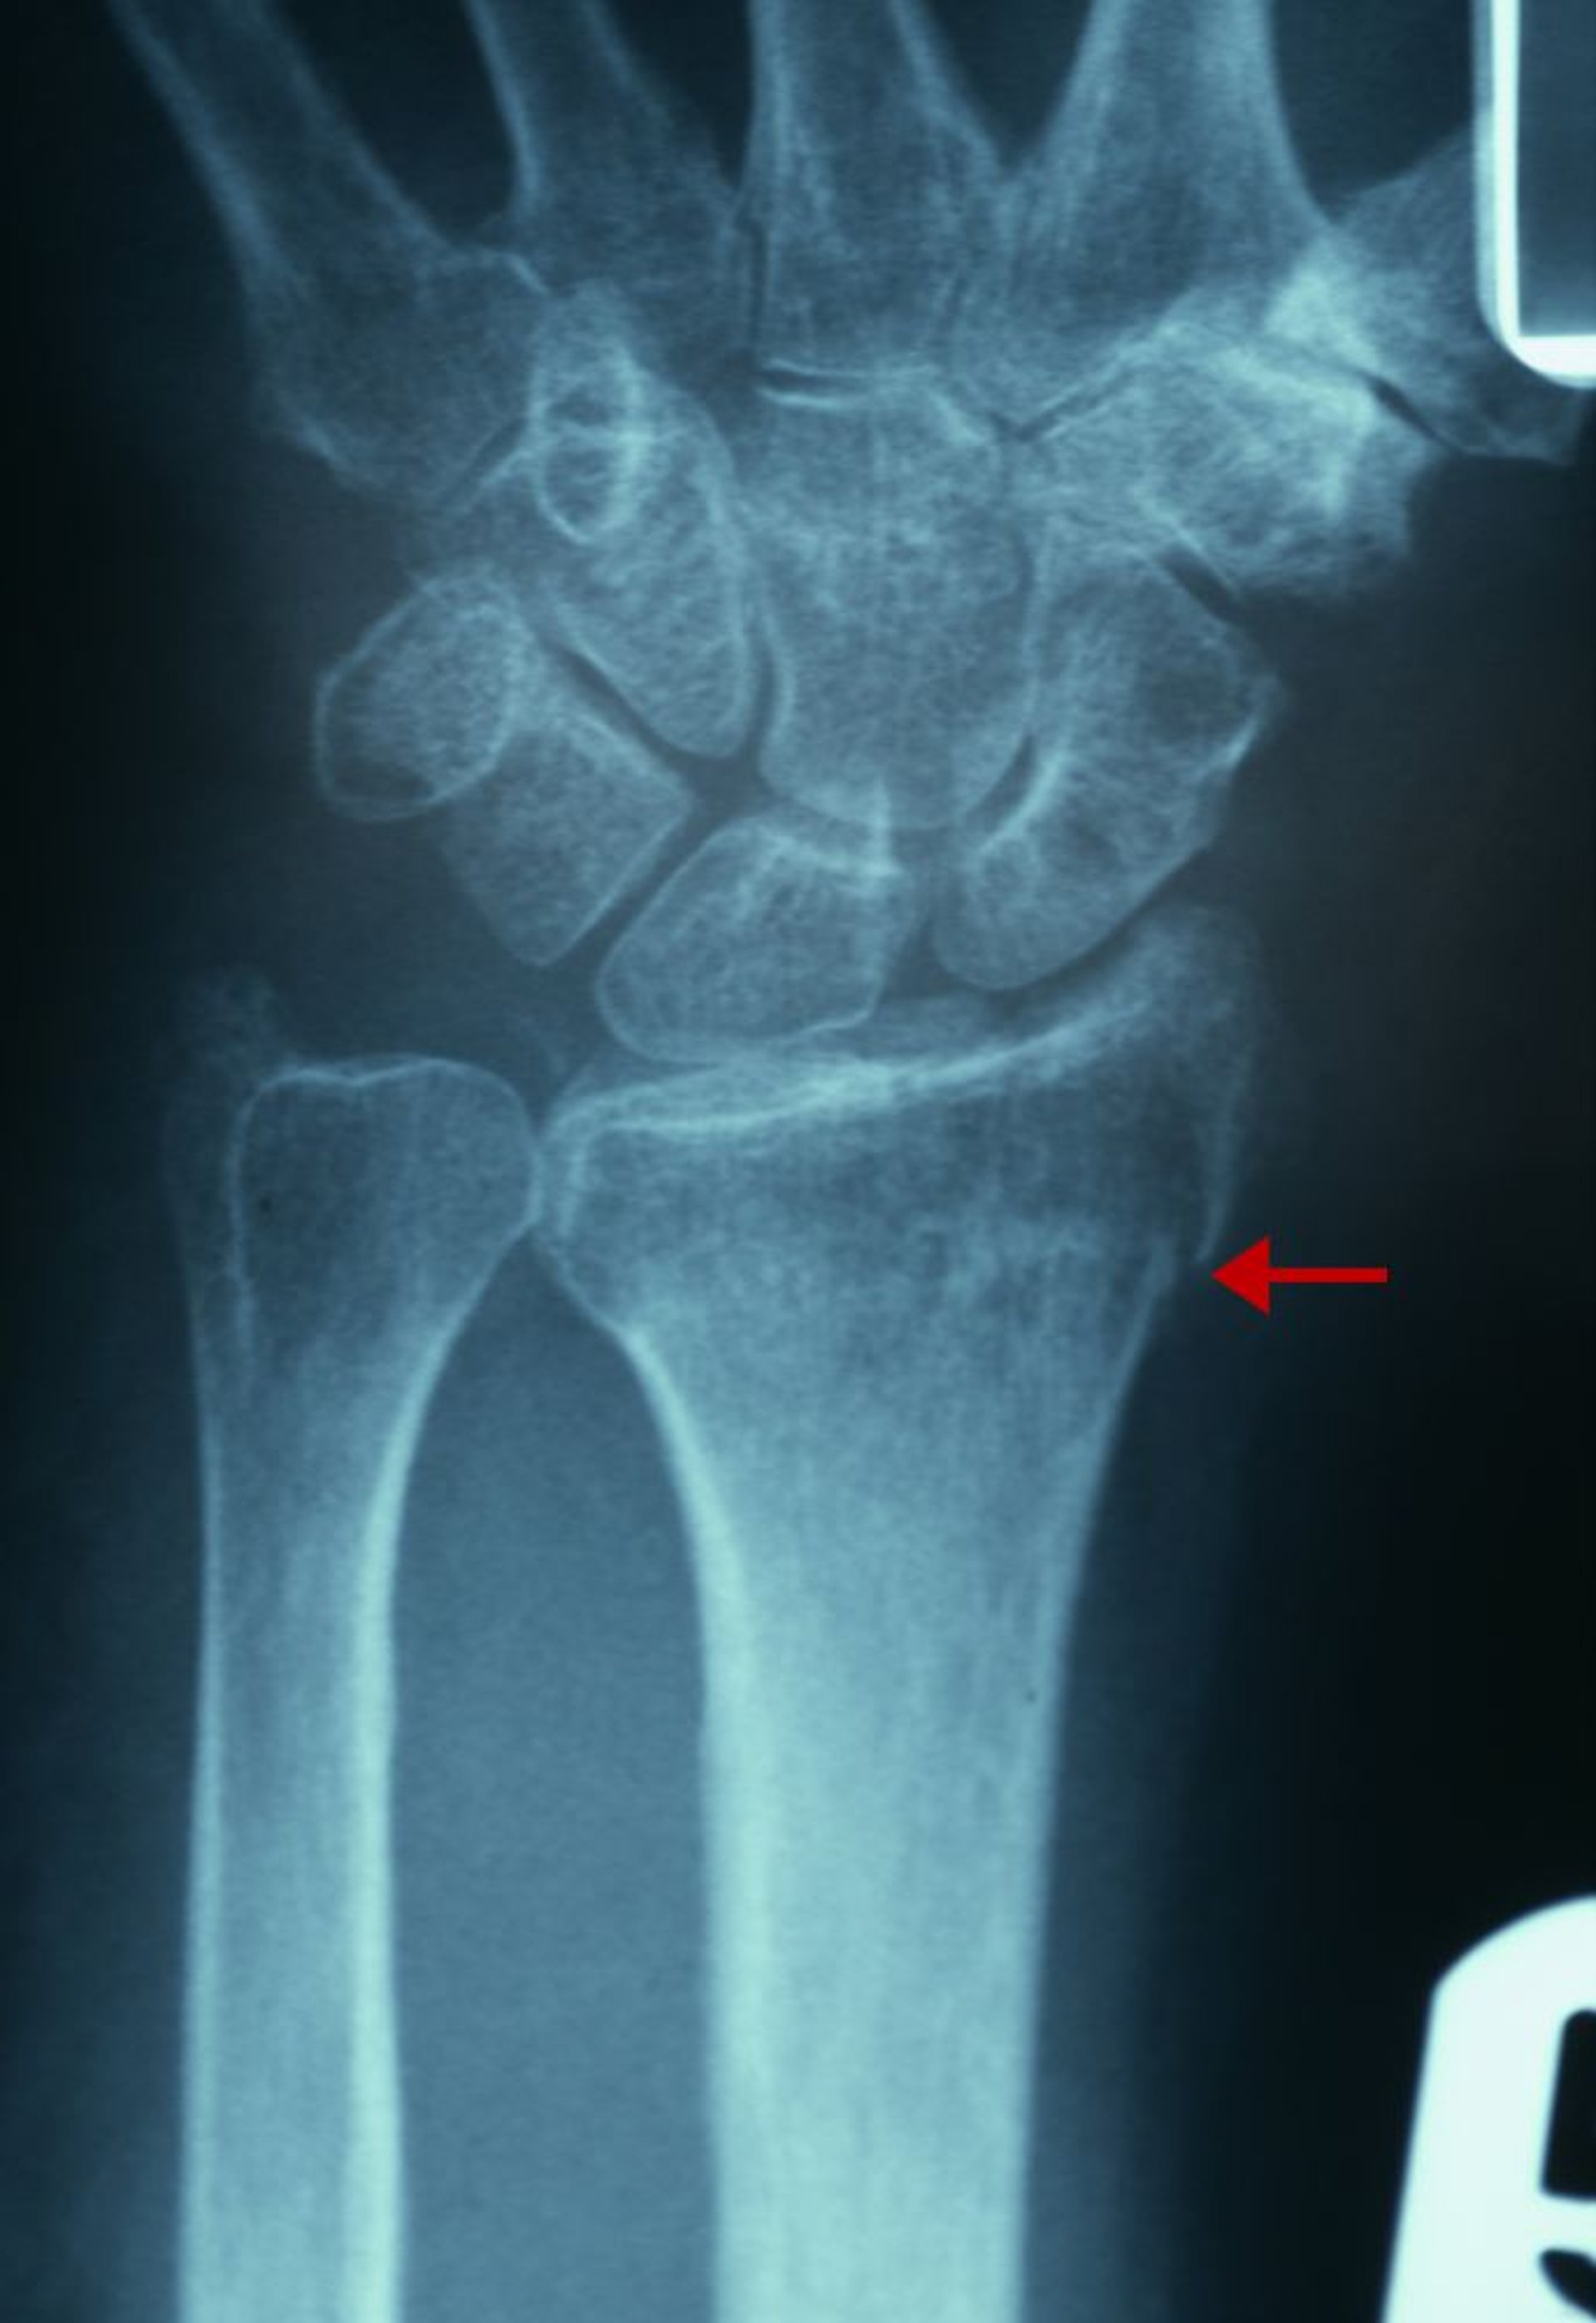

微妙な橈骨遠位端骨折

この骨折のX線所見としては,橈骨遠位部における橈側面の皮質にみられる連続性の途切れ(矢印),橈骨遠位部における海綿骨の密度増加などがある。